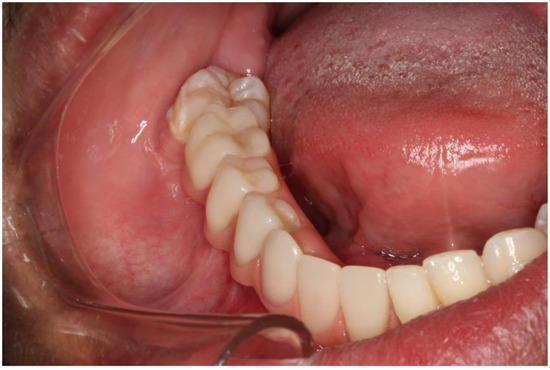

2.1. Case 1

2.2. Case 2